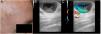

CASE 1: We present the case of an 80-year-old woman with a bluish papule of indeterminate time of evolution located on the left cheek (Fig. 1). The lesion was asymptomatic. Ultrasound showed a subdermal hypoechoic cystic lesion with turbulent color Doppler flow (Fig. 2). Venous ectasia was suspected and surgical removal was performed. The final histopathology diagnosis was hidrocystoma. CASE2: The second case was a 72-year-old man with a translucent nodule in the right temple (Figure 3). Clinical diagnosis was suggestive of a hidrocystoma. In the US exploration we also observed a hypoechoic cystic lesion with turbulent color Doppler flow (Figure 4). Final histopathology diagnosis was consistent with clinical diagnosis of hidrocystoma.

Chin and associates evaluated several hidrocytomas using US. They suggested that these structures showed a cystic lesion with hyperechoic surface and either a hypoechoic center (lipofuscin debris) or an echolucent center (clear fluid).3 Perez-Lopez et al. stressed the absence of flow inside this structures.4 However, in our cases we have seen that sometimes this structures can show positive Doppler signal.

In our cases, the movement of the interior material of the hydrocystoma led to an image in the color Doppler that can be incorrectly interpreted as vascular flow.